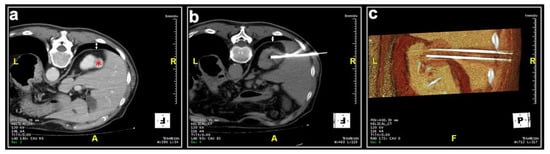

Most patients (87.4%) were treated prone. Twenty patients were treated in the oblique or lateral decubitus position (Figure 1). Only two treatments were carried out with the patient supine. Local anesthesia was mostly sufficient for the large majority of the procedures and mild conscious sedation was administered if needed. One patient required general anesthesia for the impossibility to collaborate with breath holds during the procedure because of dementia. In most cases, one lesion was treated in each procedure. In five patients, two lesions were treated in the same procedure, and, in another two patients, three lesions and four lesions were treated in a unique procedure, respectively. A median of two cryoprobes were used for each intervention (range: 1–8). Eight cryoprobes were required for the treatment of one of the largest tumors (5.4 cm), which revealed to be a clear-cell carcinoma at biopsy. The procedure was technically successful, and no complications occurred. Eighty-nine lesions required a complex cryoprobe approach. Hydro-dissection was necessary for the treatment of 13 tumors due to the vicinity of the bowel that could not be displaced after changing the position of the patient (Figure 2). In two cases, emptying of a cyst adjacent to the lesion was deemed necessary. Only one patient required a trans-hepatic approach (Figure 3). The procedures had a median duration time of 84 min (range: 40–153). Data on radiation exposure was available for 113 out of 138 patients with a median radiation exposure of 43.7 mSv.

Figure 1. Male, 73 years old. (a) Preparation of the treatment of a lesion located at the upper pole of the left kidney (*). The initial scan shows the interposition of the costophrenic sinus (white arrow). (b) The patient was positioned in an oblique decubitus, on the same side of the costophrenic sinus, to free the path for the two cryoprobes and the lesion was adequately treated without pneumothorax.